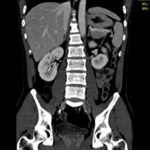

その輪切りにした画像を重ね合わせて、上からみた画像はこのようになります。

さらに進んで、3D処理をするとこのようにみえます。

腎臓や腹部大動脈がよく見えますね。